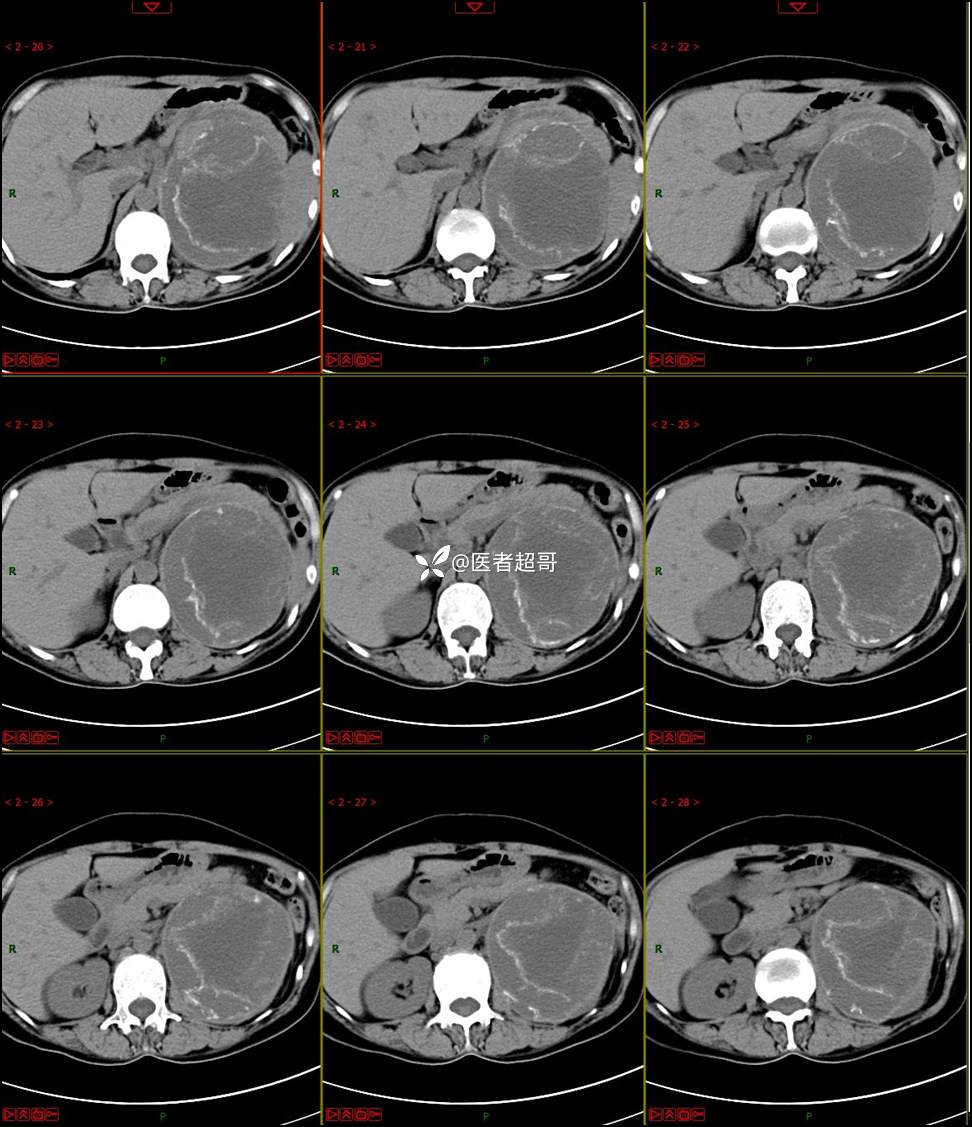

【影诊笔记768】肾脏肿瘤?肾上腺肿瘤?请诊断分析!

女 57岁 0200908 01

主 诉:发现左肾肿物7月余

现病史:患者7月前因左侧腹部疼痛不适,就诊市人民医院,行CT平扫:左侧肾上腺区混杂密度肿块,考虑肿瘤合并出血,行保守治疗后症状缓解出院,左侧下腹部及左侧髋部疼痛不适,无尿频、尿急、尿痛,无肉眼血尿,无寒战、发热,今患者为求进一步诊治,就诊我院,门诊以“左肾肿物”为诊断收入院,患者自发病以来,神志清,精神可,饮食睡眠可,小便如上述,大便正常,体重未见明显改变。